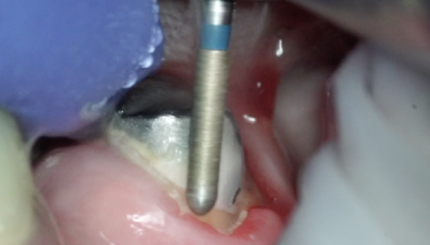

Препарирование зуба 36, с низкой клинической коронкой